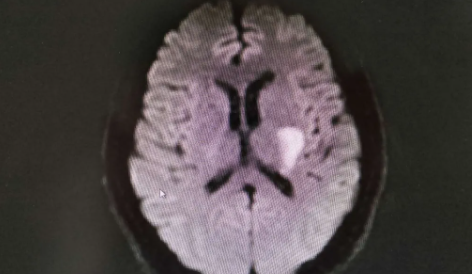

近日,48歲的大明(化名),因“言語含糊、右側偏癱24小時”入院。大明是一位小有名氣的畫家、雕刻家,而這個年齡,也正是他創(chuàng)作生涯的“登峰”時刻,但不幸的是,也許明叔再也都難以回到昔日的“黃金歲月”了。

原來,大明突然出現(xiàn)一側手腳無力的剎那,意識到自己得了腦中風,沒錯!但腦海里首先想起的竟然是網(wǎng)上盛傳的——針刺“放血”大法。于是,他讓家人用縫紉針放血十個指尖和雙耳垂。

初時,大明自覺癥狀似有好轉,滿心歡喜。于是大明選擇繼續(xù)在家觀察。結果,第二天起床時,竟然走不了路,方讓家人立刻送到醫(yī)院。可是,這個時刻,已然錯過了最佳的治療時機(6小時內)。